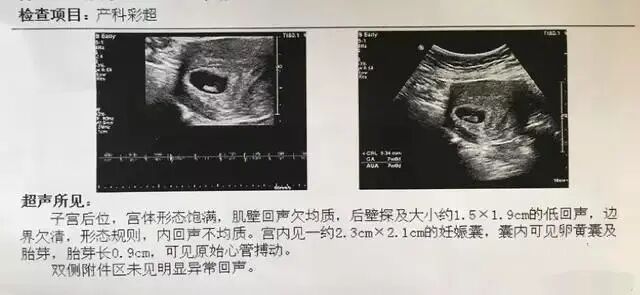

妊娠囊也叫孕囊,一般在7-8周的时候能清晰地看到孕囊,这时孕囊的直径大约为2厘米。孕囊内还有卵黄囊和胎芽。如果孕囊在宫内,就说明胚胎在宫内安营扎寨了。

7-8周做B超时也能看到胎芽,胎芽的长度有一个具体的标准,详细见下表。

7-8周的B超也能看到原始的胎心搏动了,以后的B超单中会显示胎心率的具体数据。